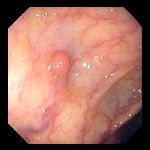

Ce que l'on observe lors d'une coloscopie

![]() |

Polype sessile

|

Des diverticules

Une diverticulite